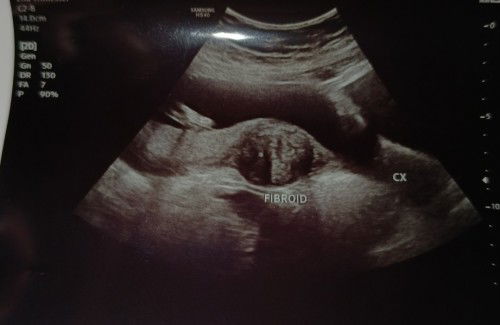

fibroid seen 19w pregnancy

Assalam Hi mmy2 smua . Klmarin sy ada buat ANATOMY SCAN kat Sonobee, alhamdulillah semua ok gender pun dh nmpak jelas . Cuma sy baru dpt tau semalam sonographer tnjuk sy detect fibroid kt laluan nk bsalin. Sonographer suh inform kt doc nanti next checkup kt KK. Tp mcm lmbt lagi hujung bulan nanti. Cuma nk tnya mmy2 , ada tak yg pernah alami mcm sy fibroid time pregnant ? Mcm mana tips nk kecutkan fibroid kot mmy2 boleh share pglaman , mmbhayakan tak utk baby dn sy nanti ? Sy due 30 July . #seriusnanya #firstmom #pleasehelp #bantusharing